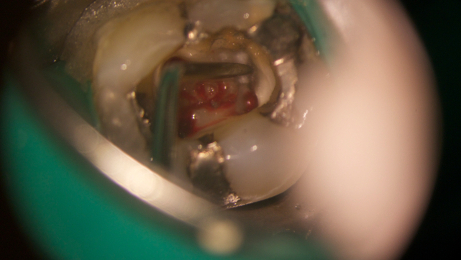

As aplicações clínicas, em que a utilização da vibração ultrassónica assume um papel de destaque, são: refinamento de cavidades de acesso, localização de canais radiculares, preparação de istmos, remoção de espigões e instrumentos fraturados, desobturação de canais radiculares, condensação de MTA e preparação apical para retrobturação em cirurgia apical.

Fotos dos casos clínicos